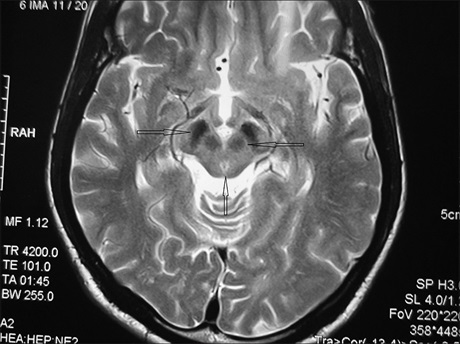

Magnetic Resonance Imaging of an Intraventricular Meningioma in a Nigerian Male

Dr. Sefiya Adebanke Olarinoye‑Akorede, Aliyu O Akano, A O Jimoh (Author)

32-35

Views | PDF/EPUB Downloads : 228 / 22 / 23

DOI: https://doi.org/10.82235/wajr.vol22no1.288